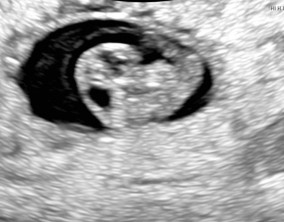

시험관 1차, 진짜 로또가 찾아왔어요

인터넷의 여러 정보들이 많아서 과연 이게 맞나? 나는 왜 다르지? 이런 고민들이 매일 밤 자기전에 찾아왔지만 이경훈 원장님을 믿고 가면 된다는 확신이 생겼습니다. 원장님만큼 …